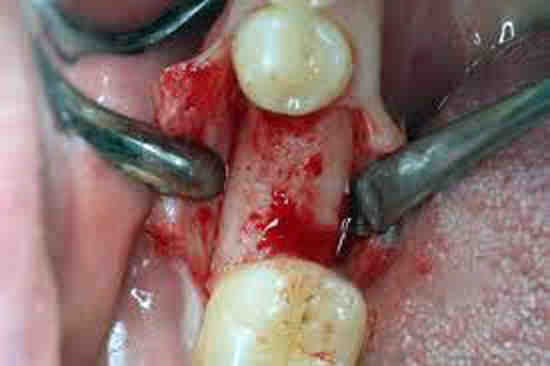

To access it, a flap-like incision is made in the gum tissue. To see also : Cost Of Full Dentures. This helps remove diseased tissue from inside the pocket and provides access to the root surfaces of the teeth for deep cleaning, which helps remove harmful plaque and tartar (tartar). Then the “flap” is closed, sealing the area.

Overview of the Surgery A flap procedure cleans the roots of a tooth and repairs bone damage caused by gum disease. A gum specialist (periodontist) or oral surgeon often performs the procedure. Before the procedure, you will be given a local anesthetic to numb (freeze) the area where the doctor will be working on your gums.